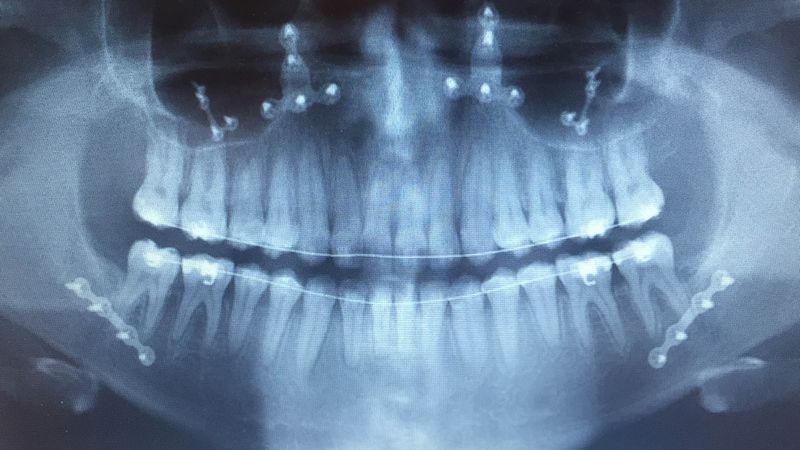

Dr. Dyer underwent orthognathic surgery himself to correct his Class III malocclusion (also known as an underbite). Having personally gone through the process, he can truly empathize with patients and offer valuable insights from a patient’s perspective, making your journey easier.

Before

After